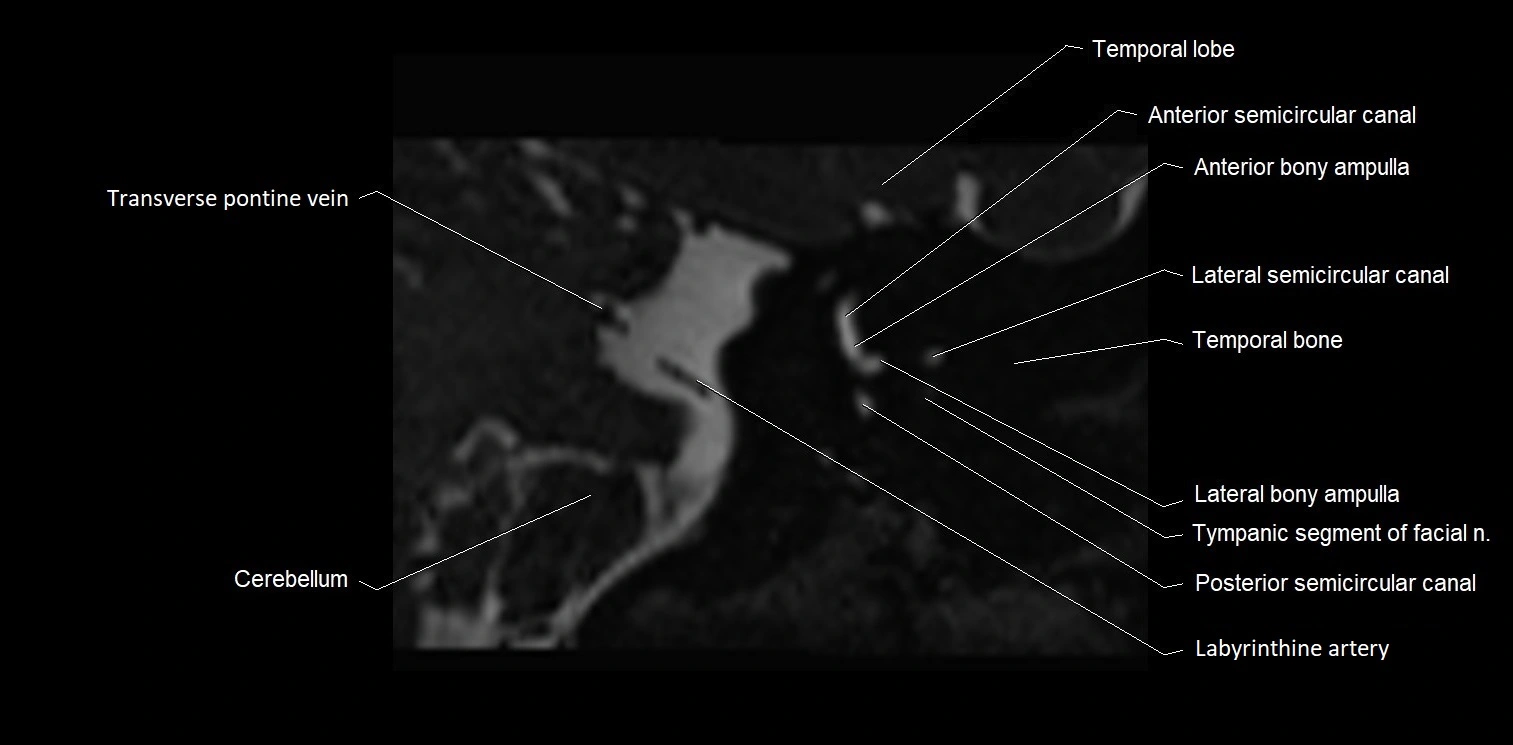

MRI Appearance

• The abducens nerve is a small, thin, linear structure

• Best visualized on high-resolution T2-weighted 3D MRI sequences (e.g., FIESTA or CISS)

• Seen as a hypointense (dark) line running from the brainstem at the pontomedullary junction, traversing the prepontine cistern, and entering Dorello’s canal under the petrosphenoidal ligament, then into the cavernous sinus, and finally the orbit

• May be challenging to visualize in standard MRI due to its small size

• Pathology may be inferred by absence, displacement, or enhancement of the nerve

MRI images

image